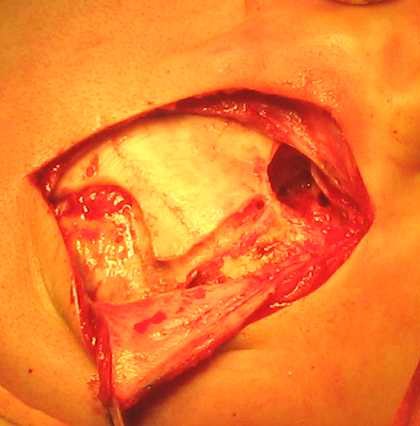

Szakasz (2. ábra) végezzük mentén átmeneti hajtás fülkagyló eltérnénk ez 1 cm. Az alsó rész közelében található a tetején a mastoid. A bőr bemetszést fölött húzódnak a felső széle a fülkagyló szinten 2 cm. Az irány ez a rész a vágott pontosan függőlegesen, és a lineáris formában.

2. ábra - A bemetszés

A hígítás után a bőr metszés és az expozíció a csonthártya és fascia halántéki izomzatot csonthártya lebeny otseparovyvayut és előrelépni, tedd visszahúzó (3. ábra).

3. ábra - a kialakulását a bőr és a periostealis szárnyak